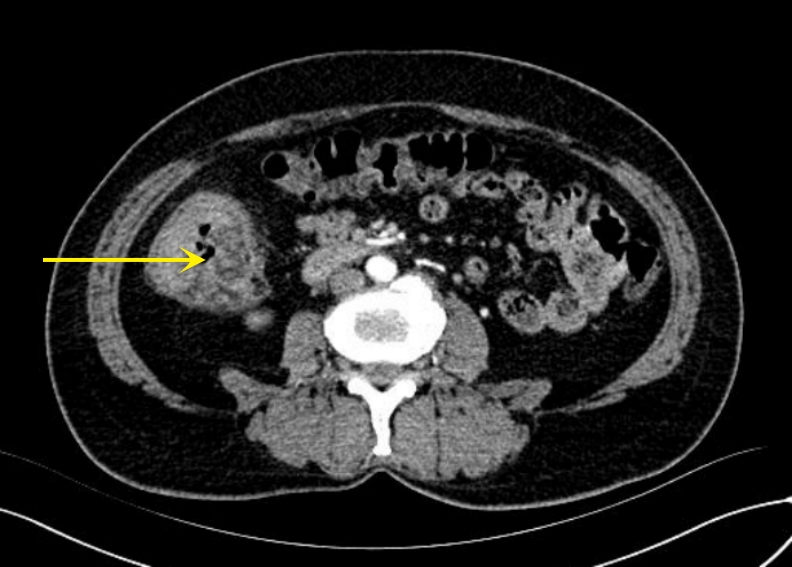

• Occult hepatocellular carcinoma presenting with humeral metastasis as the initial manifestation: a case report and literature review

2026, 35(1):141-148. DOI: 10.7659/j.issn.1005-6947.250622

Abstract (79) HTML (119) PDF 1.24 M (183) Comment (0) Favorites

Abstract:Background and Aims Hepatocellular carcinoma (HCC) presenting initially with bone metastasis is uncommon, and metastasis to the appendicular skeleton is particularly rare. These cases often lack typical liver disease history, elevated alpha-fetoprotein (AFP), or characteristic imaging findings, leading to frequent misdiagnosis or delayed diagnosis. This study reports a rare case of occult HCC presenting with humeral metastasis and reviews the literature to improve clinical recognition and management.Methods The clinical data of a 42-year-old male patient presenting with humeral metastasis as the initial manifestation admitted in August 2025 were retrospectively analyzed, including laboratory tests, multimodal imaging findings, histopathological and immunohistochemical results, treatment, and follow-up outcomes. Relevant literature was also reviewed.Results The patient presented with left shoulder pain. Imaging revealed osteolytic destruction of the left humerus. PET/CT incidentally detected multiple hepatic lesions without significant FDG uptake. Contrast-enhanced ultrasound demonstrated atypical enhancement patterns, initially suggesting a perivascular epithelioid cell tumor. Histopathological and immunohistochemical examination of biopsy specimens from both the humeral and hepatic lesions confirmed moderately differentiated hepatocellular carcinoma with humeral metastasis (CNLC stage IIIb). The patient received systemic therapy with sintilimab plus bevacizumab, followed by transcatheter arterial chemoembolization. After 6 months of follow-up, the intrahepatic lesions had decreased in size, the bone metastasis remained stable, and pain symptoms were significantly relieved.Conclusion HCC presenting with humeral metastasis as the initial manifestation is extremely rare and may lack typical imaging and serological features. Clinicians should consider HCC in patients with unexplained bone metastasis even in the absence of liver disease history or elevated AFP. Multimodal imaging and pathological biopsy are essential for accurate diagnosis and appropriate management.